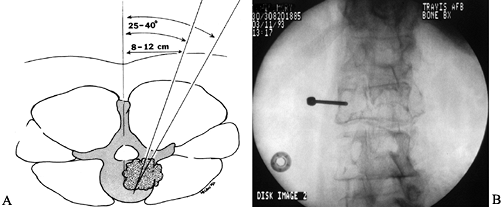

that are easily distinguished histologically, needle biopsy is ideal (Fig. 152.2).

Figure 152.2. A:

Percutaneous needle biopsy of the thoracolumbar spine is performed

through a posterior, percutaneous route. The needle is positioned 8–12

cm lateral of the midline at the level of the documented lesion. By

advancing the needle at a 30° to 45° angle, under fluoroscopic control,

the posterolateral aspect of the vertebral body is targeted. B:

Alternatively, a small posterior exposure is made over the documented

lesion, and a burr is used to take down the cortex overlying the

pedicle. A Craig needle or a small curet is then passed down the

pedicle to harvest bone and tumor from the vertebral body. -